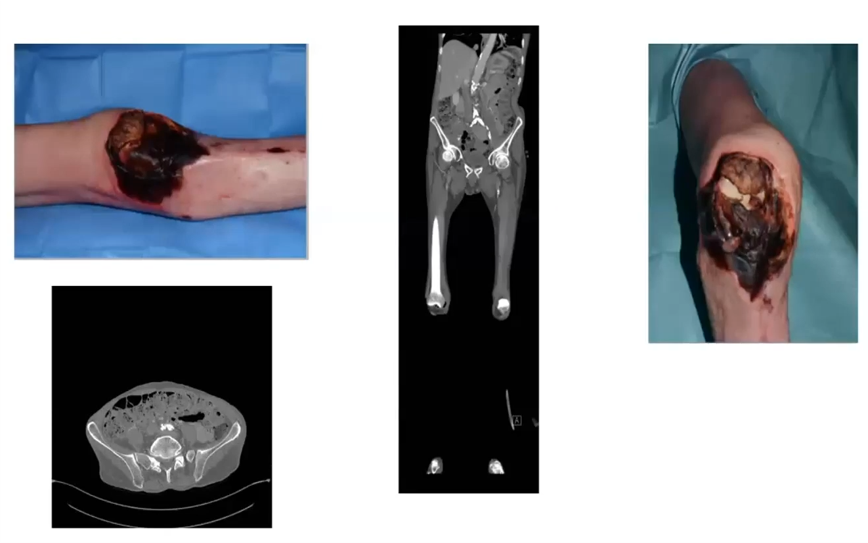

1- DM, neuropathy, IHD, war veteran and contralateral below knee amputation

What investigations?

How do you manage this ulcer?

Any room for preserving the limb?

How do you council the patient?

2- Cachectic, self-neglect

What do you want to do to this patient?

Can you salvage the limb and why?

What do you think the patient’s best interests are?